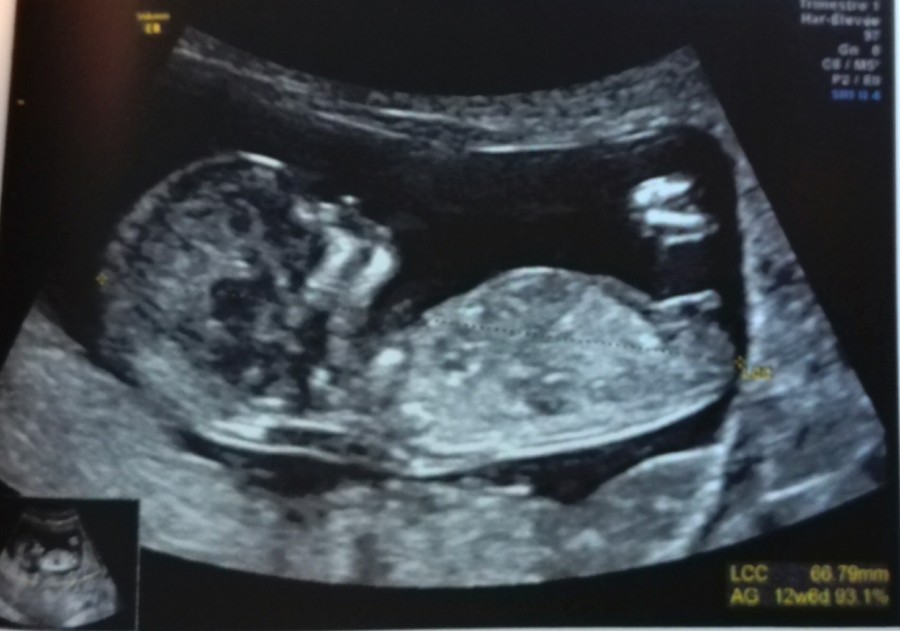

Sinon, pour l'écho, je voulais vous partager l'écho et savoir ce que vous pensiez du sexe du bébé, car avant de la faire, j'étais persuadée de ressentir que c'était une fille, ce que l'échographe m'a confirmé sans que je ne lui dise

(Même si on ne peut pas se fier à 100% à cette écho, 12+3)